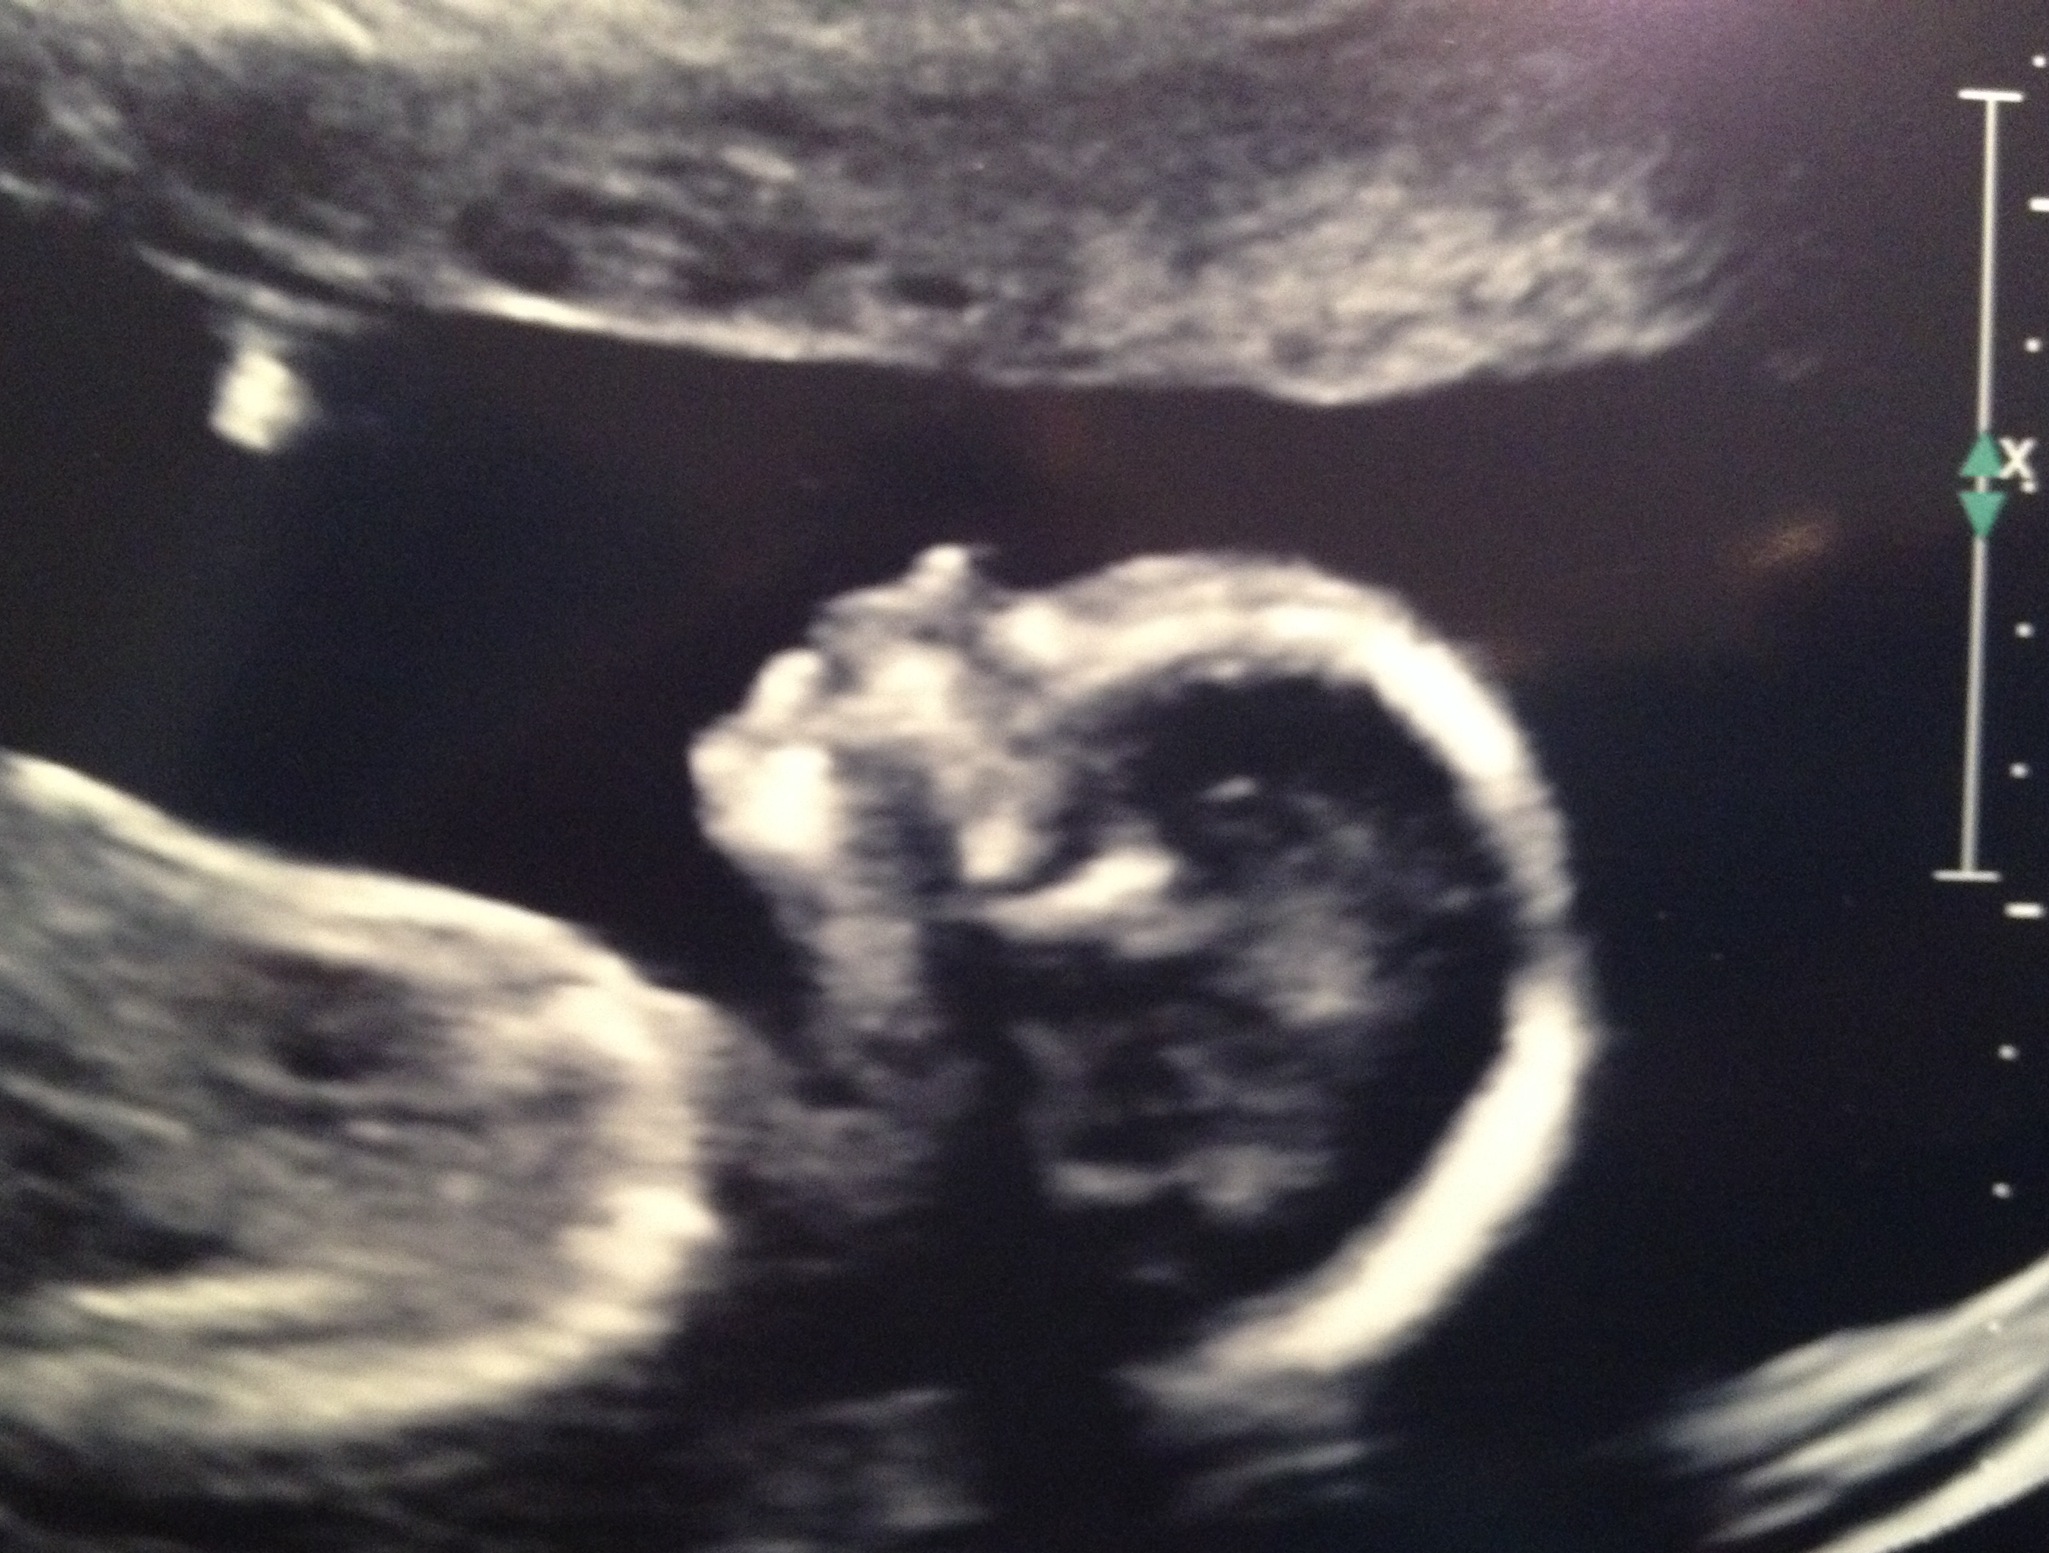

Here is the baby at my 6 week ultrasound! Attachment 15780